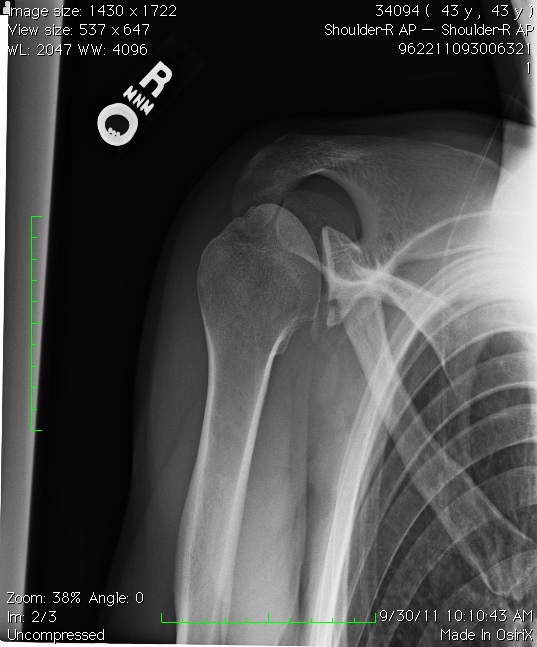

How to read Shoulder joint fracture X Ray । Scapula fracture XRay How To Fix Shoulder Fracture Learn about the different types of shoulder fractures, how they occur and how they are treated. Learn how long it takes to recover from a shoulder fracture, depending on the severity and treatment of the injury. Find out the common causes of clavicle, humerus and scapula fractures. Learn about the types, causes and symptoms of shoulder fractures, including scapula fractures,. How To Fix Shoulder Fracture.